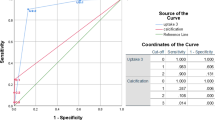

All 18 RA patients regardless of age had AA calcification on CT scan, while no calcification was detected in the AA in seven healthy controls. The average NaF-TBRmean scores among RA patients were significantly greater than that of healthy controls (median 1.61; IQR 1.49–1.88 and median 1.40; IQR 1.23–1.52; P = 0.002). The average CT calcium volume score among RA patients was also significantly greater than that of healthy controls (median 1.96 cm3; IQR 0.57–5.48 and median 0.004 cm3; IQR 0.04–0.05, P < 0.001). There was no difference between the average FDG-TBRmean scores in the RA patients when compared to healthy controls (median 1.29; IQR 1.13–1.52 and median 1.29; IQR 1.13–1.52, P = 0.98) (Fig. 3). There was no statistically significant correlation between NaF-TBRmean and FDG-TBRmean (ρ = − 0.18, P = 0.46), whereas there was a positive correlation between NaF-TBRmean and CT calcium volume score in RA patients (ρ = 0.62, P = 0.005) (Fig. 4). An inverse but statistically insignificant trend was found between FDG-TBRmean and CT calcium volume score (ρ = − 0.31, P = 0.20). Moreover, a significant positive correlation was observed between age and CT calcium volume score (ρ = 0.59, P = 0.008) but not NaF-TBRmean (ρ = 0.40, P = 0.09).

Box plot comparison of NaF and FDG uptake in the abdominal aorta as well as CT calcium volume score of RA patients and the matched healthy controls. NaF-TBRmean and CT calcium volume score were significantly higher among RA patients than that of matched healthy controls (P = 0.002, P < 0.001, respectively). FDG-TBRmean was also higher in RA group but the difference was not statistically significant (P = 0.98)